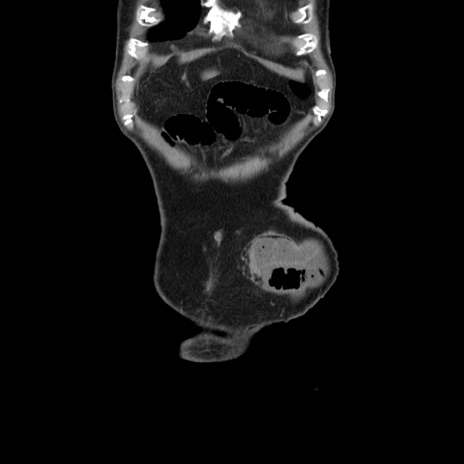

症例24(冠状断像)

【症例】80歳代男性

【主訴】左側腹部痛、嘔吐

【現病歴】本日早朝より左腹部に痛みあり。昼頃嘔吐認めたため、救急要請。

【既往歴】直腸癌(Mile手術)、胆摘

【身体所見】意識清明、BT 35.9℃、BP 221/93mmHg、SpO2 97%(RA) 、腹部:左ストーマ周囲に限局性の腹部膨隆あり。 膨隆部自発痛・圧痛あり・軟。

【データ】WBC 7700、CRP 0.09